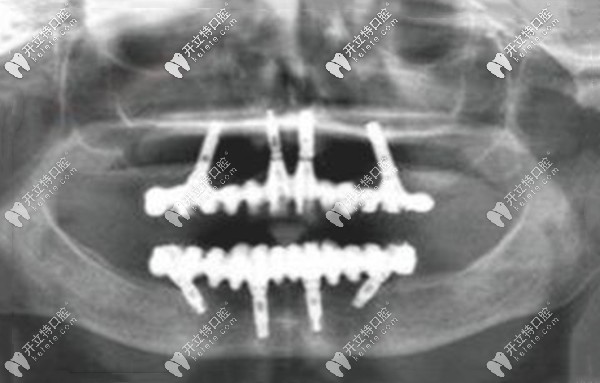

從上圖可以看出,高先生的滿口只剩下兩顆“搖搖欲墜”的牙齒,牙槽骨明顯能看出來吸收、萎縮,高度明顯降低;這就是之前假牙脫落的真正原因。

爾睦口腔肖步挺醫(yī)生對高先生的口內(nèi)拍CT片檢查后,評估了牙槽骨的厚度、密度、高度、上下頜的咬合關(guān)系,為其設(shè)計(jì)了目前比較先進(jìn)的All-on-4全口咬合重建的種植牙方案。

allon4即刻負(fù)重種牙,也就是上、下頜各植入4顆植體(兩顆純直植入、兩顆傾斜植入),再搭配覆蓋義齒,就能發(fā)揮全口的咬合力,而且是當(dāng)天種、當(dāng)天戴臨時(shí)牙冠、當(dāng)天就能吃東西。

深圳沙井爾睦口腔肖步挺院長給高先生做的allon4全口種植牙,全程用的是數(shù)字化種植方式,傷口比較小、安全性也高,比較適合老年人的半口及全口無牙的情況~~~